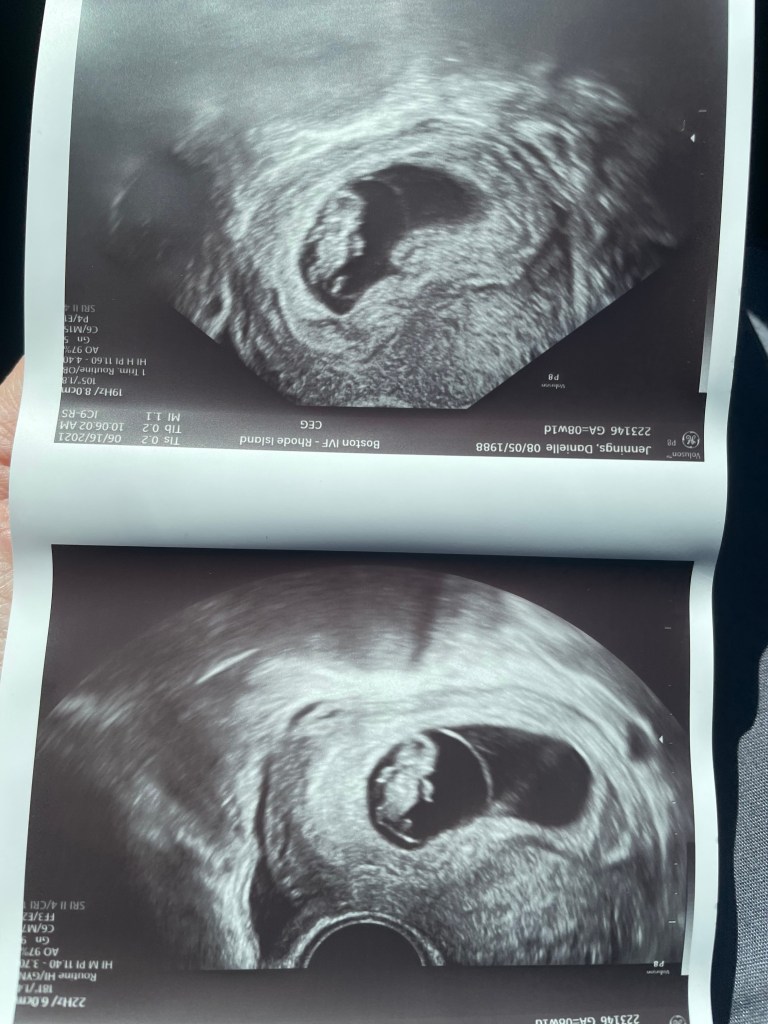

6/16/2021- 8w1d. Wow this one was the first sono that actually looked like a baby, it is amazing how much can change in just 2 weeks. We saw little limbs and baby has a strong heartbeat. We received the phone call a few hours later that I was being discharged from IVF and that I would need to schedule my next appointment with an OB. I had such mixed feelings with this news, of course everyone wants to be done with the IVF process but the thought of not getting that constant monitoring and a whole team working on your case is hard. Thankfully I used to work at my OB office so I know I am in great hands but it’s still a difficult transition.